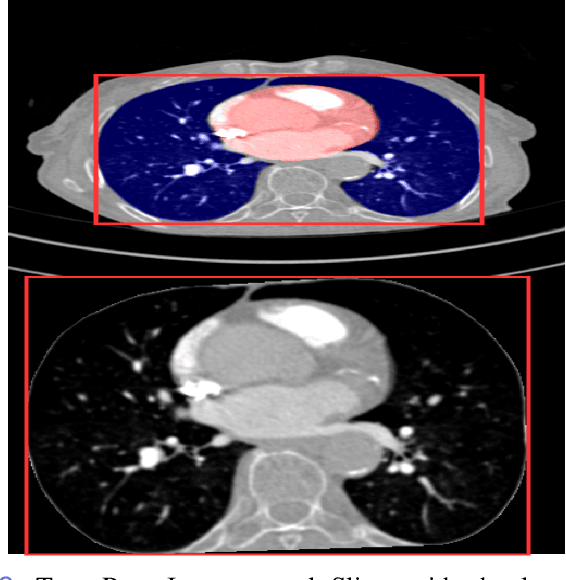

Pulmonary Embolisms (PE) represent a leading cause of cardiovascular death. While medical imaging, through computed tomographic pulmonary angiography (CTPA), represents the gold standard for PE diagnosis, it is still susceptible to misdiagnosis or significant diagnosis delays, which may be fatal for critical cases. Despite the recently demonstrated power of deep learning to bring a significant boost in performance in a wide range of medical imaging tasks, there are still very few published researches on automatic pulmonary embolism detection. Herein we introduce a deep learning based approach, which efficiently combines computer vision and deep neural networks for pulmonary embolism detection in CTPA. Our method features novel improvements along three orthogonal axes: 1) automatic detection of anatomical structures; 2) anatomical aware pretraining, and 3) a dual-hop deep neural net for PE detection. We obtain state-of-the-art results on the publicly available multicenter large-scale RSNA dataset.